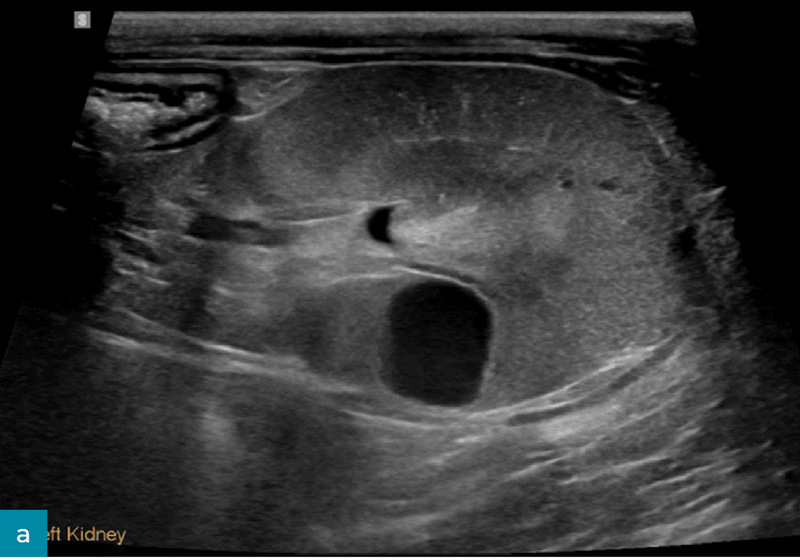

Torbiele nerek

Torbiele nerek (ryc. 12) występują częściej w korze nerkowej i mogą mieć charakter nabyty lub wrodzony. Dlatego też nie stanowią one czułego wskaźnika przewlekłej choroby nerek u psów, jeżeli nie mamy do porównania wcześniej wykonanego badania.8,17 Torbiele nerek są często stwierdzane u psów z przewlekłą chorobą nerek i zazwyczaj nie wpływają istotnie na czynność narządu. Mogą jednak zmieniać kształt nerek i być jednym z czynników powodujących nieregularność ich brzegów.8,12,21

Ryc. 12. Obraz w projekcji strzałkowej (a) i poprzecznej (b) lewej nerki psa, uzyskany odpowiednio za pomocą głowicy mikrokonweksowej i liniowej. W centrum kory nerkowej widoczna jest dobrze odgraniczona, gładko obramowana, cienkościenna, okrągła, bezechowa torbiel ze wzmocnieniem dalszym. Kora nerkowa wykazuje słabo zdefiniowane hiperechogeniczne prążkowanie oraz zmniejszone zróżnicowanie korowo-rdzeniowe. Łagodna pielektazja (wysokość miedniczki nerkowej < 2 mm) była głównie uznawana za wtórną do diurezy (na przykład fizjologicznej, spowodowanej dożylnym podaniem płynów bądź niewydolnością nerek). Obraz w projekcji strzałkowej dodatkowo wykazuje poprawę rozdzielczości przestrzennej przy użyciu głowic liniowych o wyższej częstotliwości.